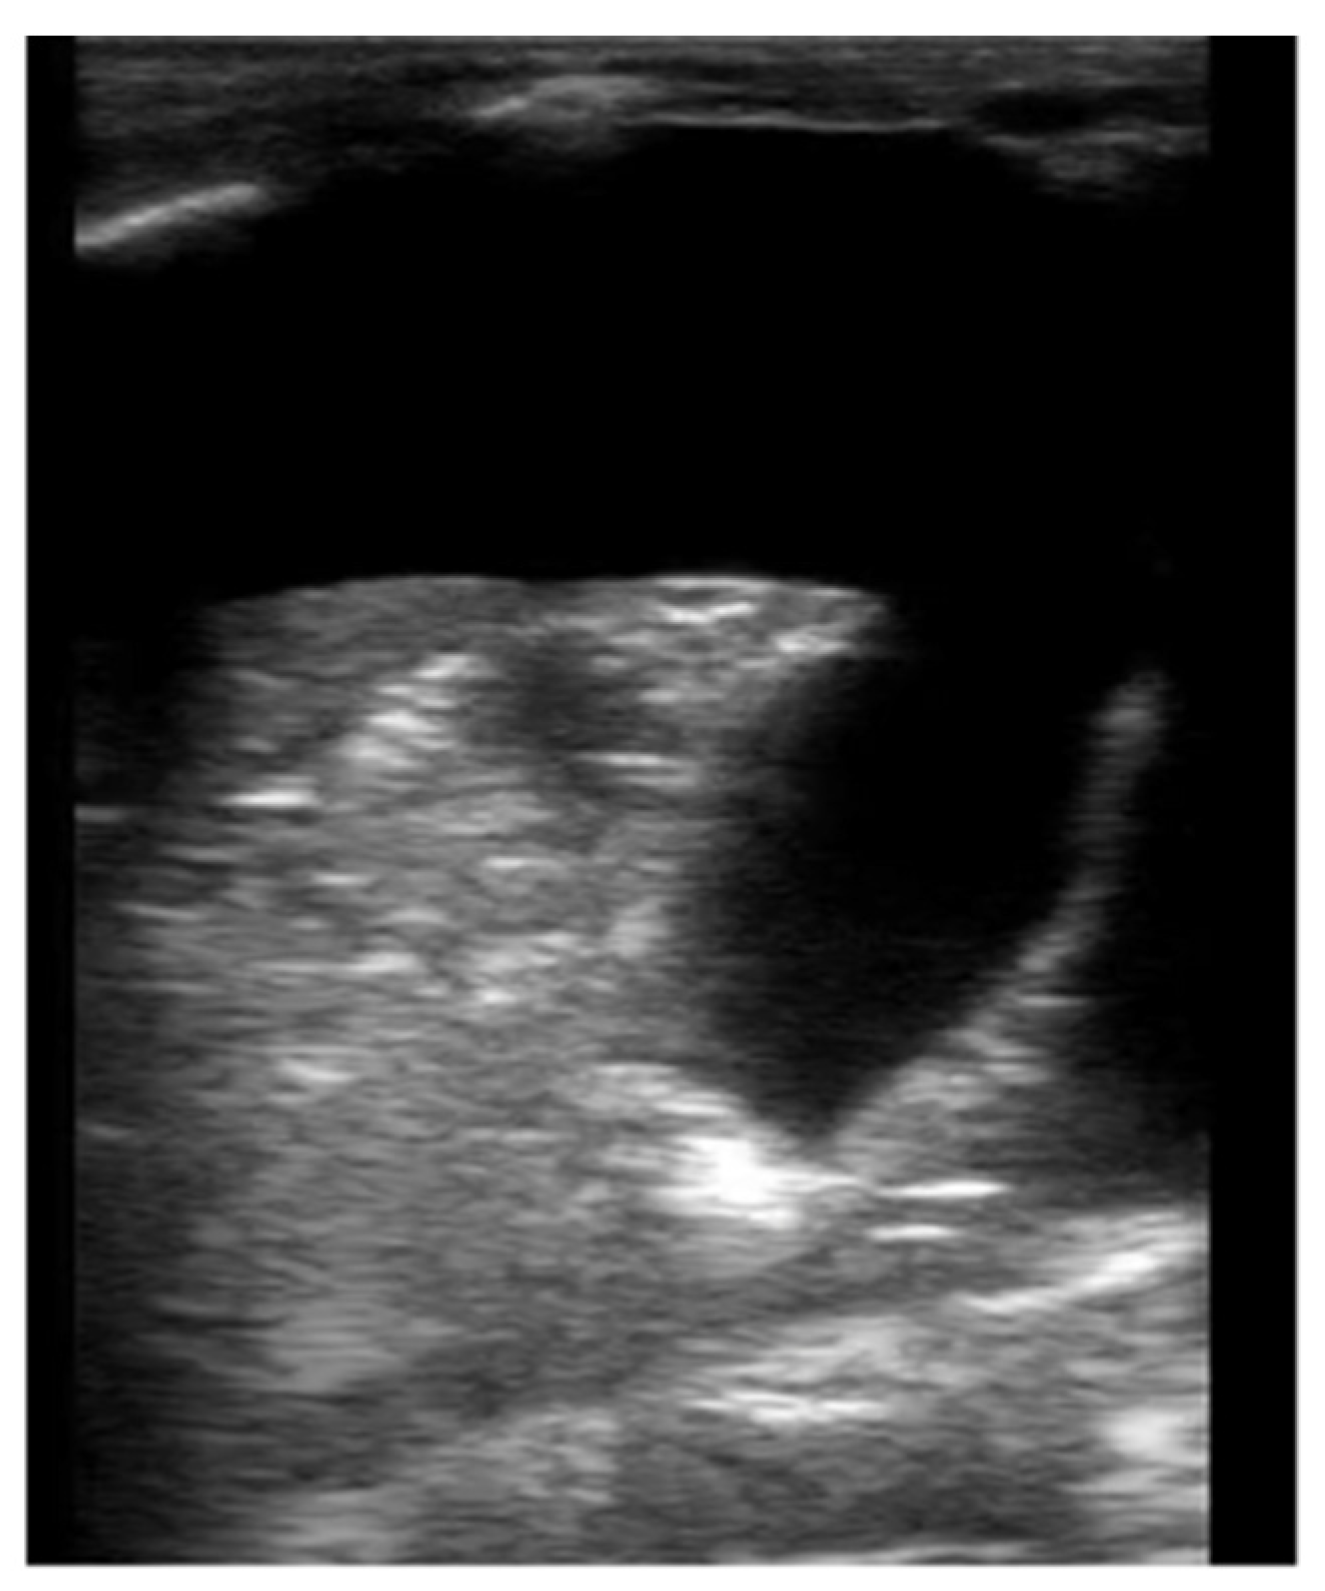

2.1. Pleural Effusion